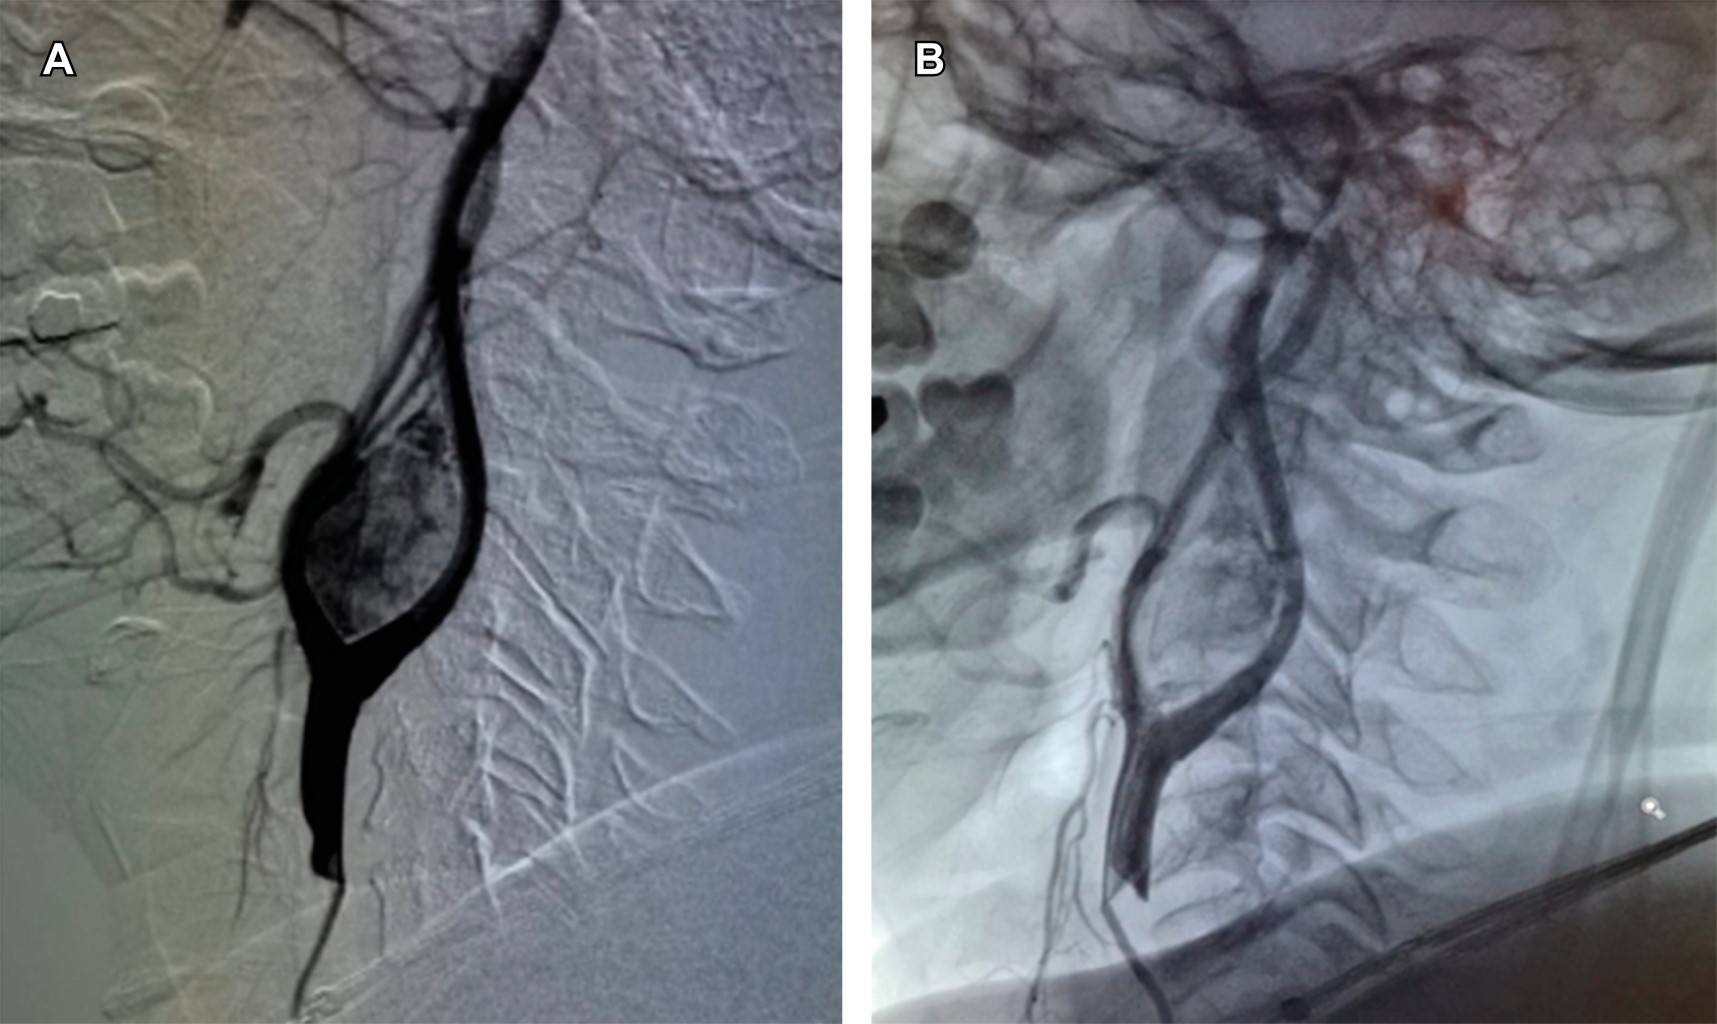

• 6. Angiografía de control, evaluando embolización exitosa (Figura 2).

En los pacientes del grupo A se logró una reducción del flujo vascular tumoral de 95% estimada en angiografía posterior a embolización.